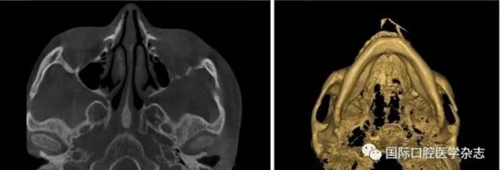

3.1.2 咬合板治療[16]

咬合板治療的適應證:顳下頜關節(jié)紊亂病。初診時取患者上下頜牙列印模和咬合記錄,牙模及咬合記錄送至同一加工廠制作牙合墊,牙合墊后牙區(qū)墊高3 mm。2周后復診佩戴,囑患者夜間佩戴,佩戴時間為每天10~12 h,連續(xù)佩戴3個月,治療期間,每月復診1次,調整咬合干擾(圖16)。

A:穩(wěn)定牙合墊;B:Twin-block牙合墊;C:患者帶入Twin-block牙合墊。

圖 16 咬合板治療